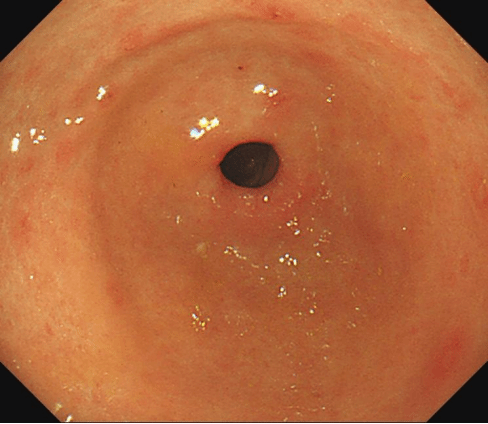

治疗前:黏膜红白相间,以白为主,白相凹陷,散见充血斑及出血点。